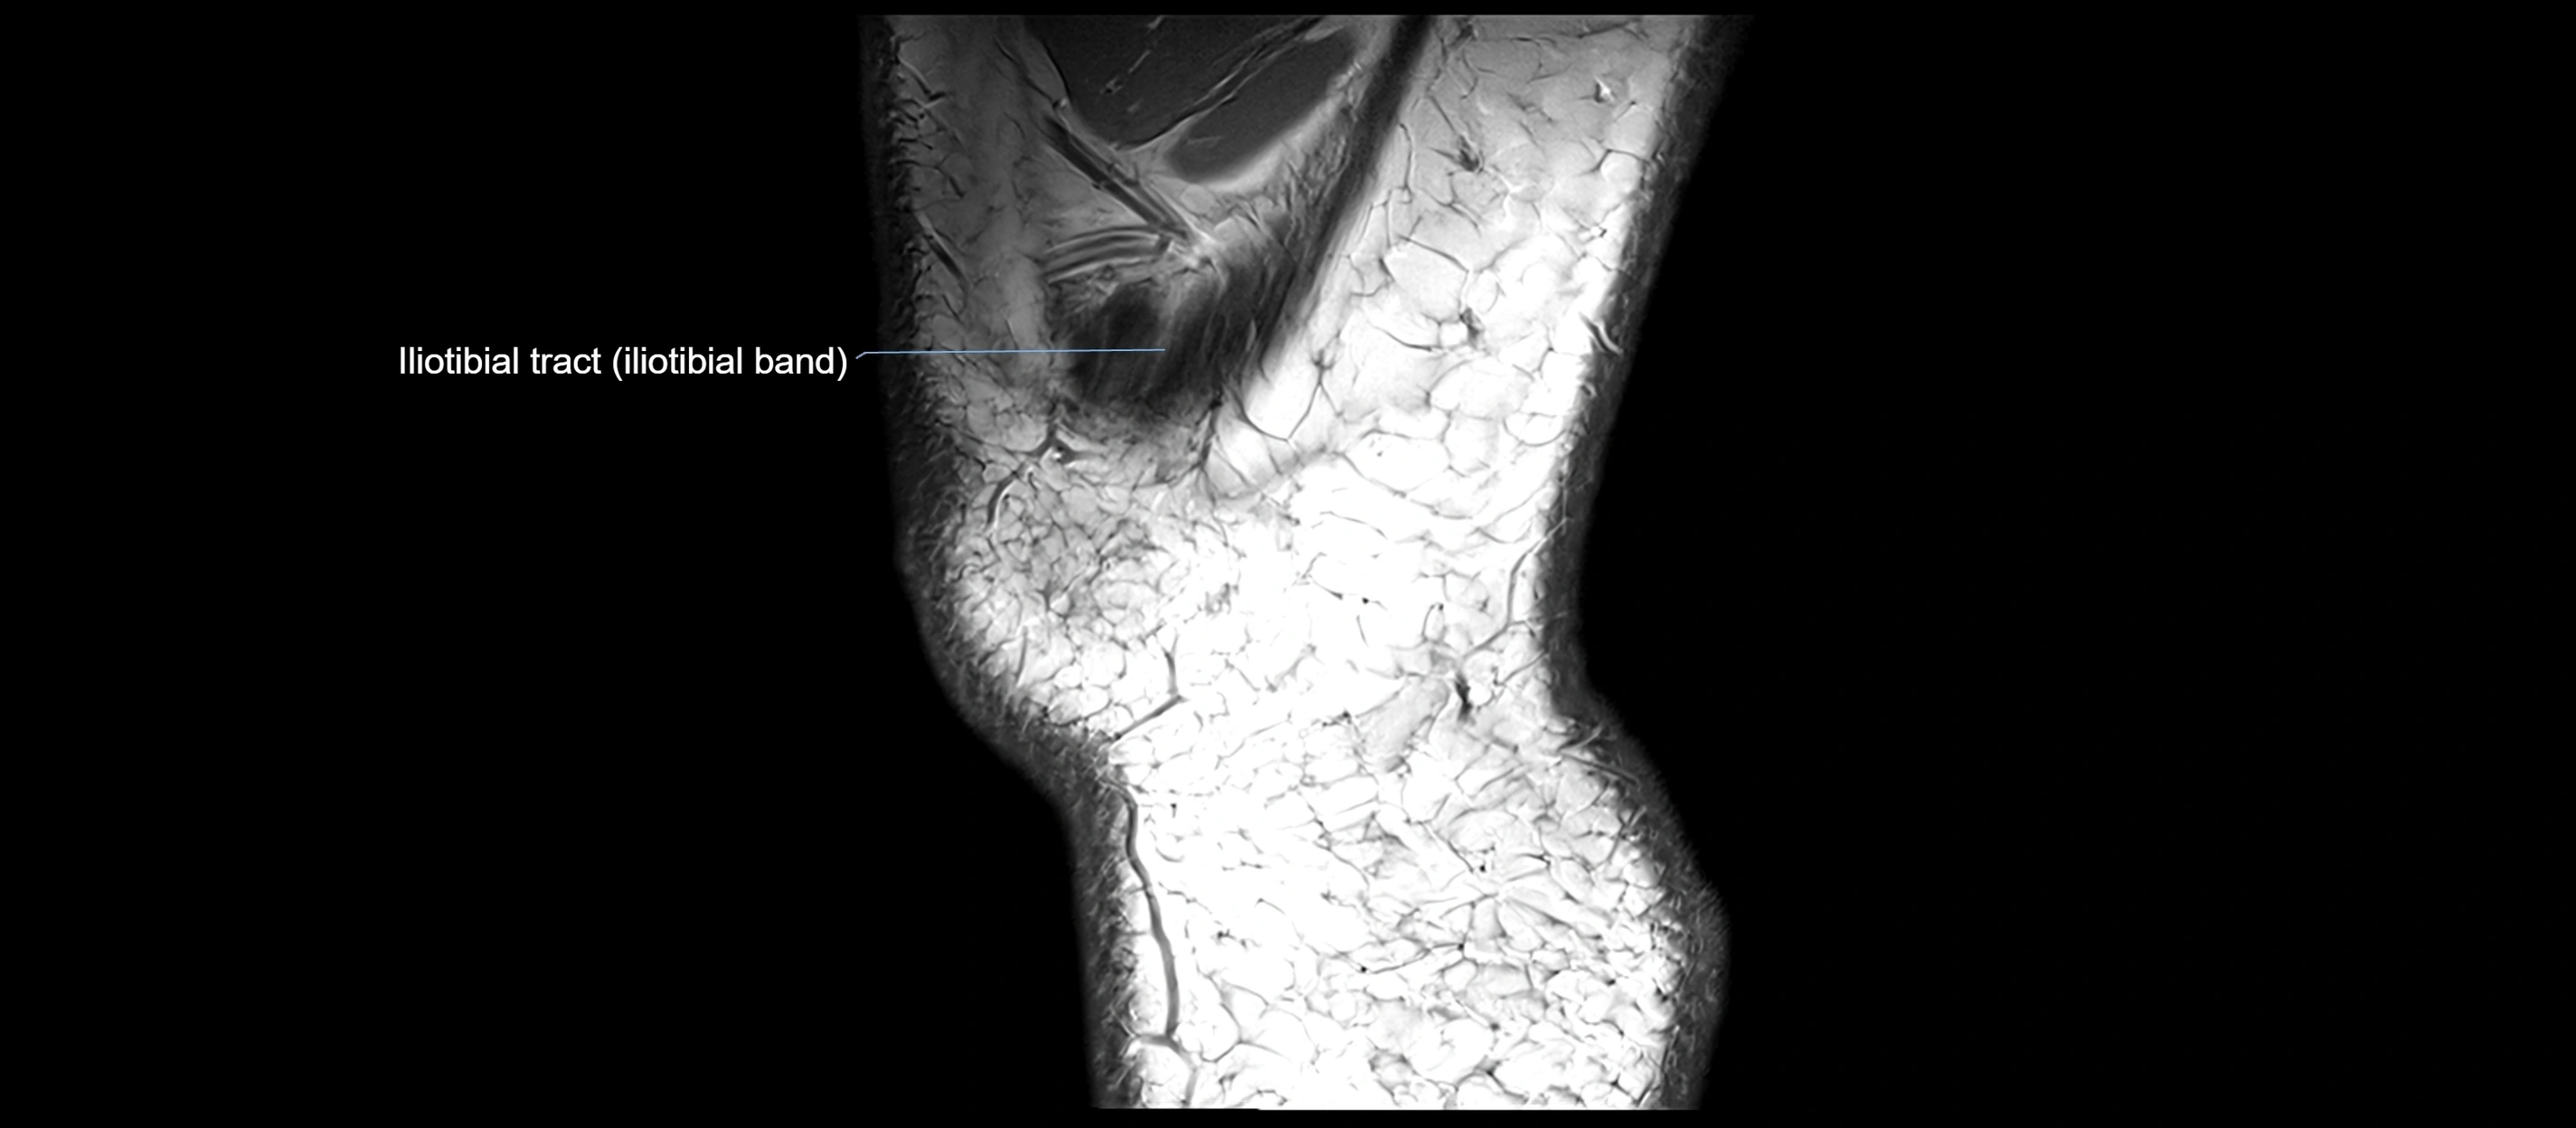

MRI Appearance

T1-weighted images:

• Normal ACL appears as a low-signal band-like structure crossing the intercondylar notch

• Surrounded by intermediate signal synovial fluid and fat planes

T2-weighted images:

• Normal ACL remains low signal

• Partial or complete tears appear as discontinuity, increased signal, or fiber laxity

MRI images

image